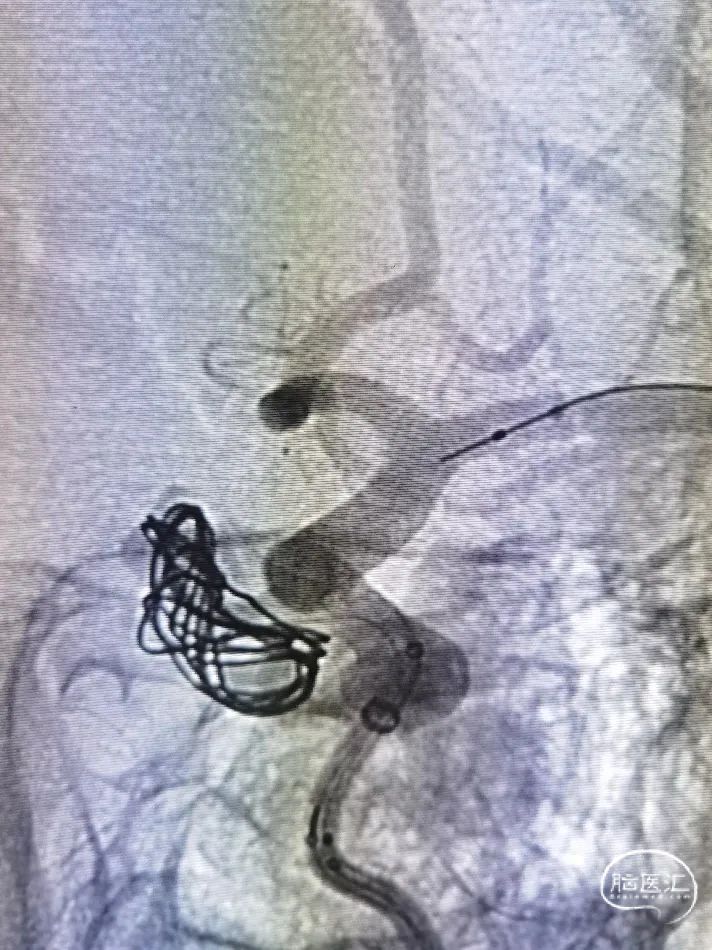

右侧股动脉入路,8F短鞘、6F长鞘在125导管及导丝引导下送入左侧颈内动脉C1段远端,经长鞘送入6F中间导管,造影确定工作位,在XT-27和微导丝引导下将中间导管送达C4段,同时XT-27进入左侧大脑中动脉M2段,塑形后SL-10进入眼段较大动脉瘤腔内,部分填入7mm弹簧圈,然后采取推拉技术于C7段开始部分释放Surpass Evolve 4.5*25mm支架先覆盖瘤颈,继续栓塞动脉瘤共3枚弹簧圈,撤出SL-10微导管,继续完成支架后半部分释放,并使用导管导丝按摩支架腔内。造影示大动脉瘤显影缓慢,瘤颈部分残余,小动脉瘤缓慢显影。三维造影可见支架贴壁良好。

支架头端打开良好,部分释放覆盖瘤颈。

支架半释放覆盖瘤颈。

继续填塞动脉瘤。

采用推拉结合支架过弯完全打开。

术毕支架展开并贴壁良好。